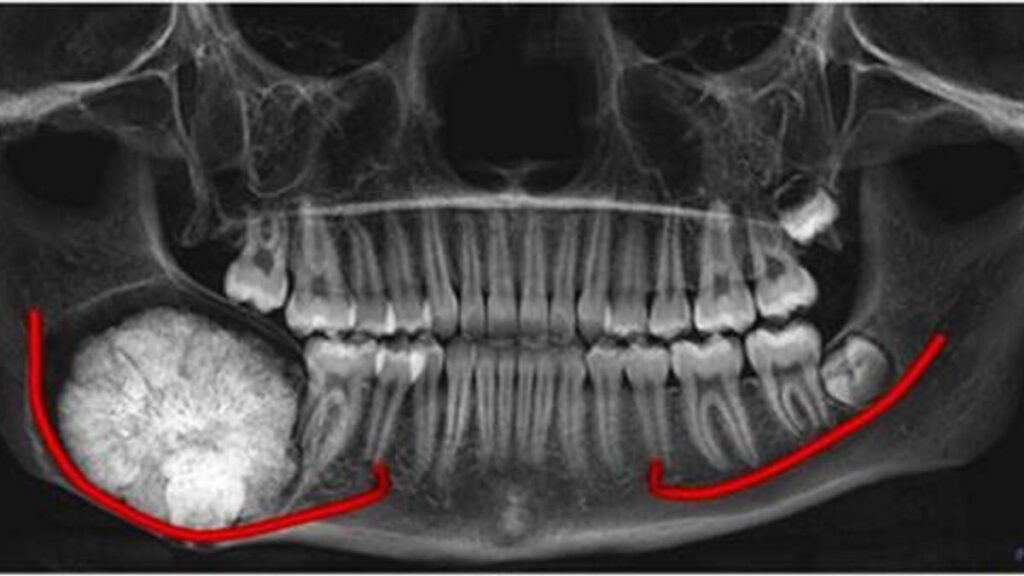

Kabaca fındık büyüklüğünde nadir görülen bir diş tümörü, yakın zamanda 14 yaşındaki bir Arap gencinden çıkarıldı ve ona tekrar gülümsemesi için birçok neden verdi.Salem Salah’ın çilesi dört yıl önce alt çenesinde sürekli şişlik ve rahatsızlık fark ettiğinde başladı. Zamanla şişlik kötüleşti ve ailesinin özel tıbbi bakım aramasına neden oldu.Ameloblastik fibroma olarak tanımlanan tümör, kabaca fındık büyüklüğünde olan 21x21x25 milimetre boyutlarındaydı. Medcare Dentofaces ağız ve çene cerrahı danışmanı Prof. Farzin Sarkarat, ”Dişlerden ve çevresindeki yapılardan kaynaklanan bu nadir tümör, genellikle gençleri etkiler ve genellikle dişsiz dişlerle ilişkilendirilir” dedi.“Tedavi edilmezse tümör büyüyebilir ve çevredeki kemiğe ve sinirlere potansiyel olarak zarar verebilir. Salem’in durumunda, yüz deformitesi veya alt çenede duyu kaybı gibi ciddi komplikasyonlara yol açarak uygun tedavi için daha invaziv cerrahi gerektirebilirdi ”diye ekledi Al Safa’daki Medcare Hastanesi’nde üç saatlik cerrahi prosedürü yöneten Profesör Sarkarat.

Salem Salah'ın tümör tarama görüntüsü. Fotoğraf: Sağlanan

İlk değerlendirme sırasında Salem’in alt çenesinde sağ üçüncü azı dişinin yerini alan belirgin şişlik bulundu. “Tümör, alt dişlerde, çenede ve dudaktaki hissi kontrol eden alt alveolar sinire tehlikeli bir şekilde yakındı. Bu, sinir hasarı riskini artırarak ameliyatı özellikle zorlaştırdı “dedi.Cerrahlar, siniri dikkatlice koruyarak ve yeniden konumlandırırken tümörü ve etkilenen bilgelik dişini başarıyla çıkardılar. Stabilite ve işlevselliği sağlamak için Salem’in çenesini yeniden yapılandırmak için bir kemik plakası yerleştirildi.